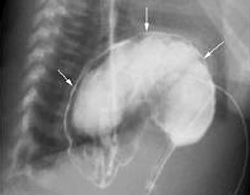

Thay vì nằm ở ổ bụng, dạ dày của bệnh nhi 7 tuổi (Bà Rịa - Vũng Tàu) lại chui lên lồng ngực. Đây là bệnh lý xoắn dạ dày ở thể rất hiếm gặp bởi thường chỉ xảy ra ở trẻ lớn hơn.

Dạ dày chui lên lồng ngực bệnh nhân. Ảnh: B.V

Tại bệnh viện, diễn tiến của bé ngày càng xấu, bụng trướng to, ói nhiều hơn. Chẩn đoán qua hình ảnh cho thấy có hiện tượng dạ dày dãn to, ứ đọng dịch. Kết quả chụp phim còn phát hiện, dạ dày của bé phần dưới bị xoắn lên cao và một phần chui lên lồng ngực.